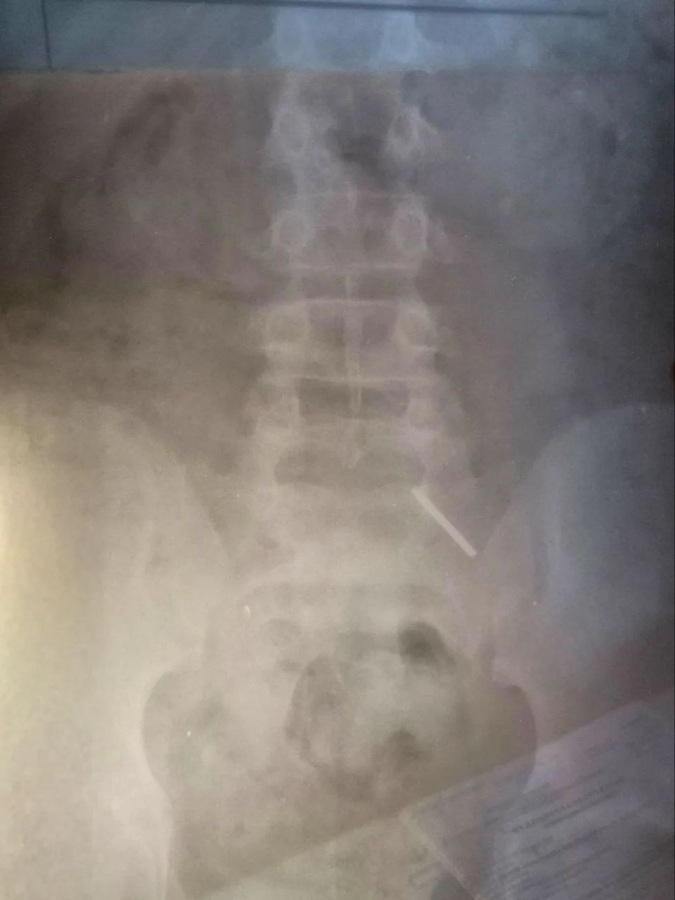

Балаковские медики в очередной раз столкнулись со случаем проглатывания инородного тела детьми. На этот раз школьник проглотил часть циркуля. Причину, по которой несовершеннолетний решился на такой опасный поступок, установить не удалось. Поскольку пациент обратился поздно, извлечь предмет эндоскопически не представлялось возможным. Основной задачей в данном случае являлось недопущение кровотечения и перфорации кишечника. Ребенок находился под наблюдением врачей и рентгенологов. В итоге инородное тело вышло естественным путем. Пациента выписали домой.